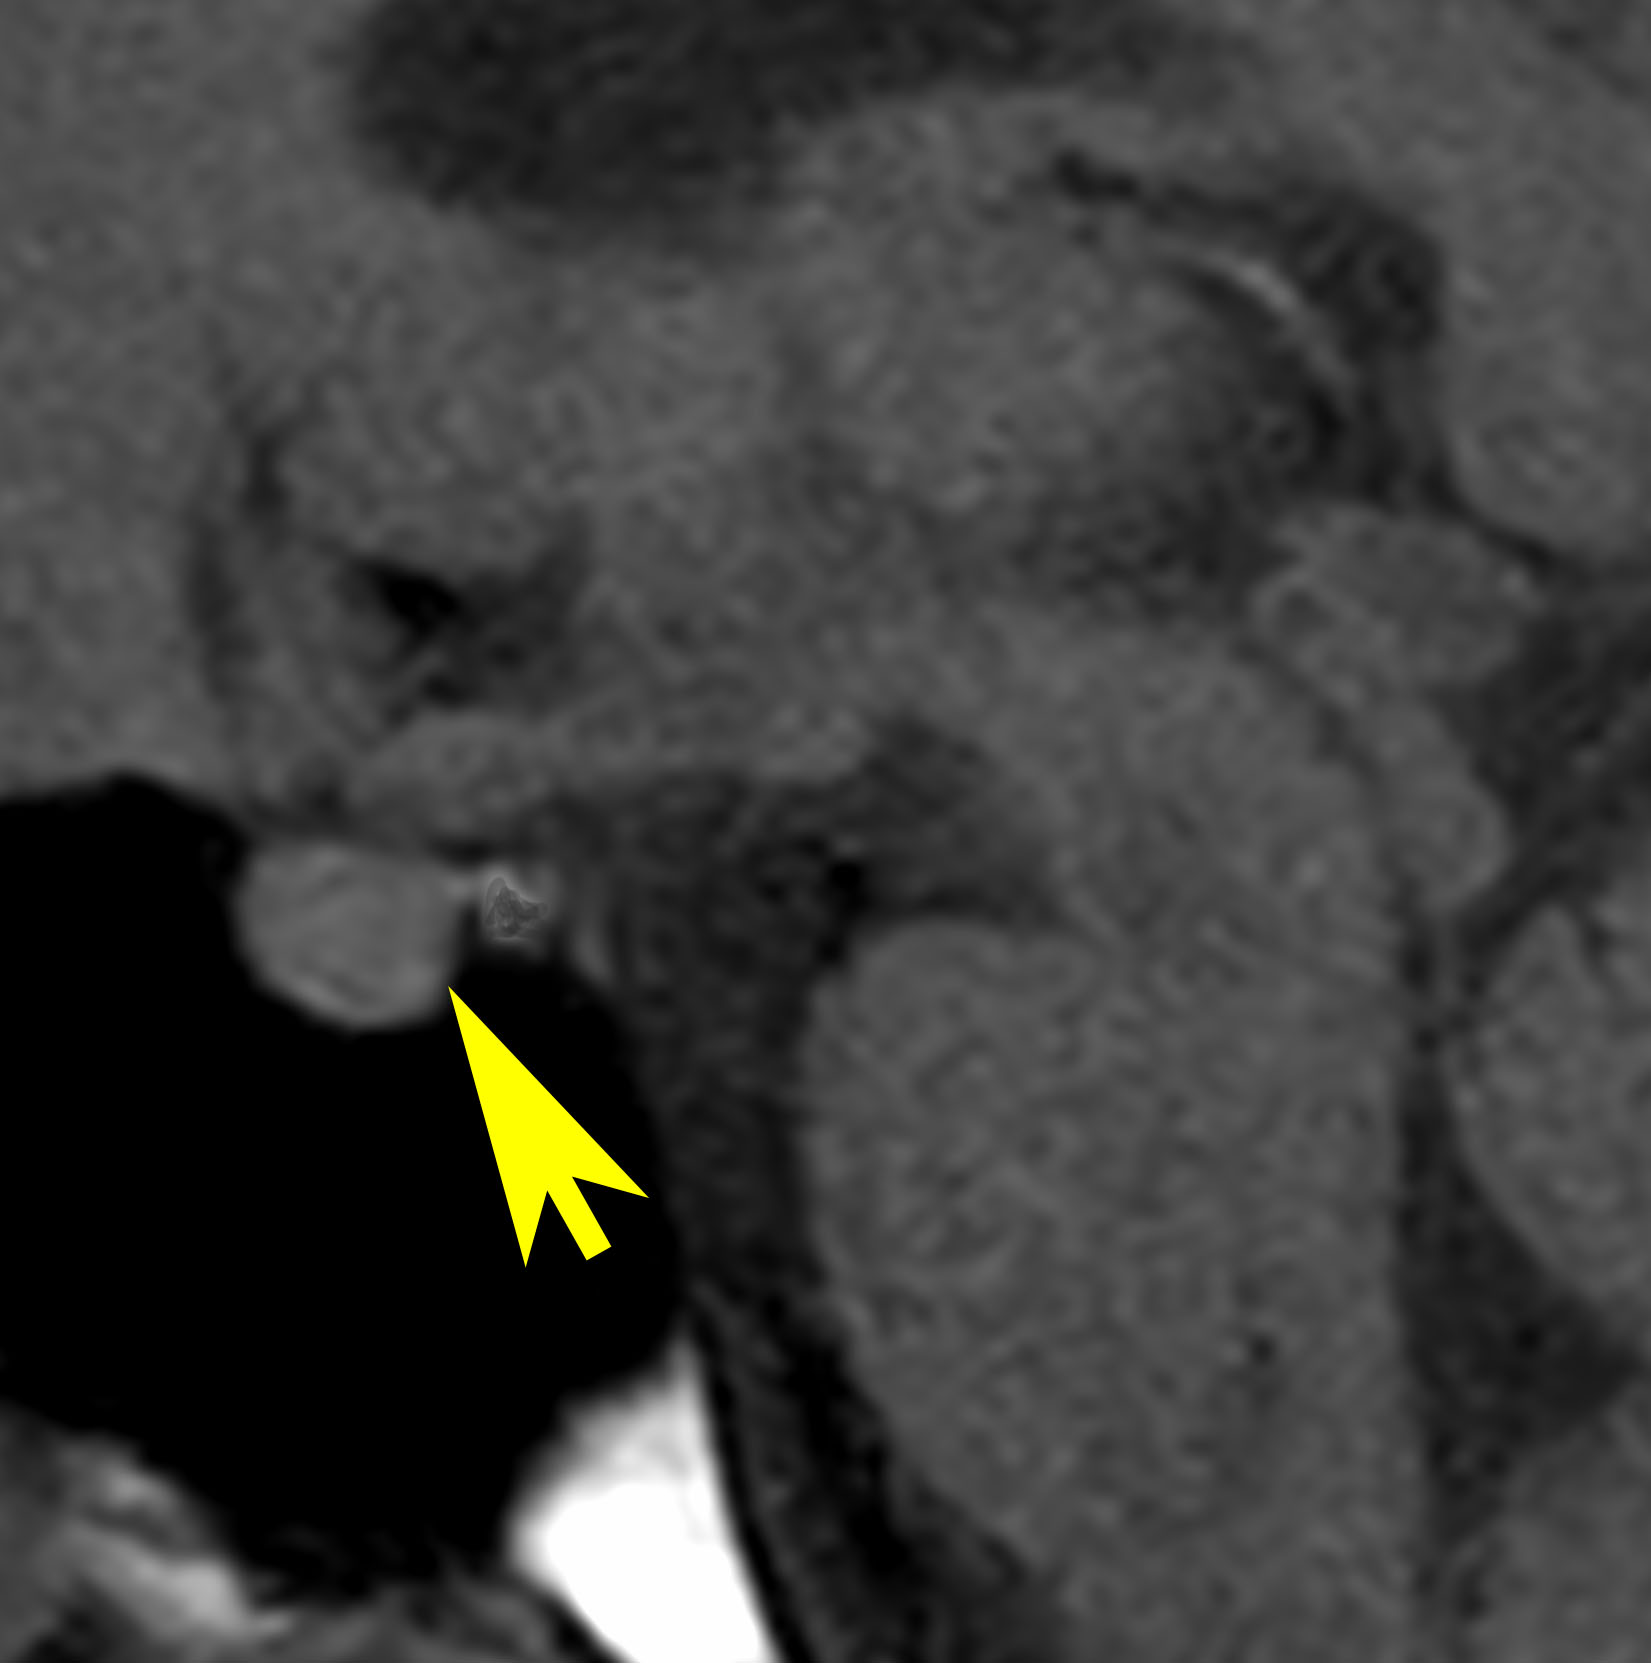

放射線が外れやすい部位は再発源となります

側脳室先端(前角,後角,側頭角,閂),下垂体と大脳基底核に放射線が入らないとその部位から再発します。

再発ジャーミノーマの画像です。延髄背側の閂 ovexという部位に再発しています。

このパターンはとても多いです。なぜかというと,全脳室照射の時に,第4脳室下端のovexの上衣 ependyum を照射野に入れない放射線治療医の先生がいるからです。放射線科の先生にもちょっとした知識が必要なのです。

これは再治療で腫瘍が消えても不可逆的な重症の延髄障害を残してしまいます。